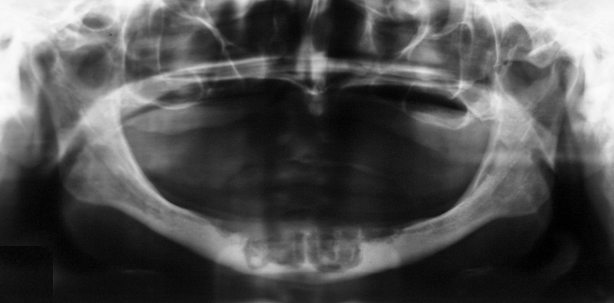

Abb. 1: Patient mit Periimplantitis sowie BRONJ. – Abb. 2: Patient nach Explantation, Persistenz der Osteonekrose mit Fraktur der Unterkieferfront.